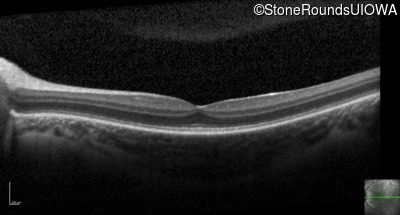

Optical Coherence Tomography - Right - 20/50 -1

Exemplar / OCT Stack

OCT Stack